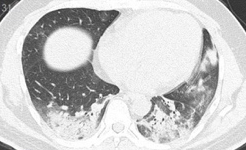

SARS-CoV-2 CT Scan dataset [50]: The dataset was collected from hospitals of Sao Paulo, Brazil, with a total of 2482 CT scans acquired from 120 patients of both genders. It is composed of 1252 scans for patients infected with SARS-CoV-2 and 1230 scans for patients infected with other lung diseases. The CT scans have varying spatial sizes between and , and are available in PNG format. CT scans from this dataset are shown in Figure 7.

COVID19-CT dataset [51]: The dataset consists of a total of 746 CT images. There are 349 CT images of patients with COVID-19 and 397 CT images showing Non-COVID-19, but other pulmonary diseases. The positive CT images were collected from preprints about COVID-19 on medRxiv and bioRxiv, and they feature various manifestations of COVID-19. Since the CT images were taken from different sources, they have varying sizes between and . Figure 8 shows example CT images from the COVID19-CT dataset.